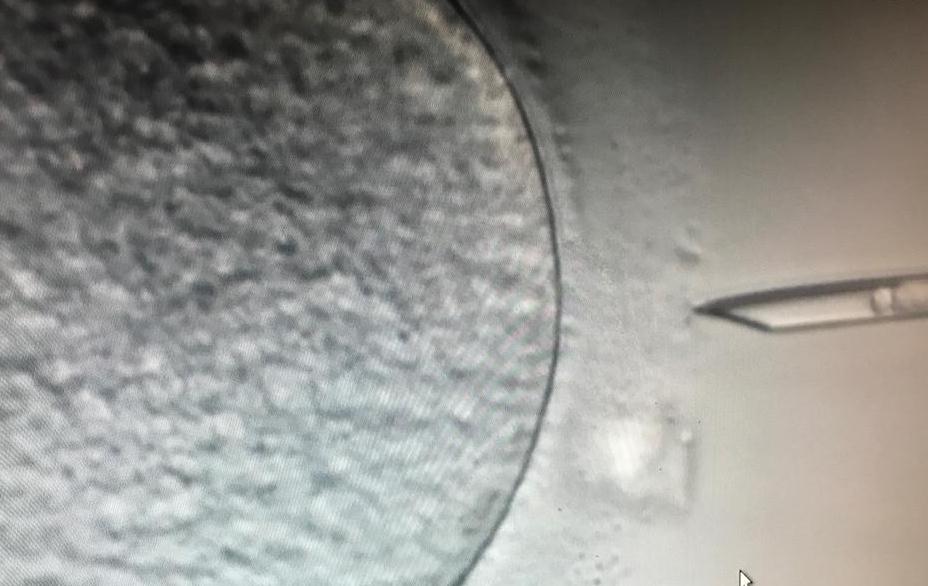

Embriyoda Genetik Tani Preimplantasyon Genetik Tani Tup Bebek